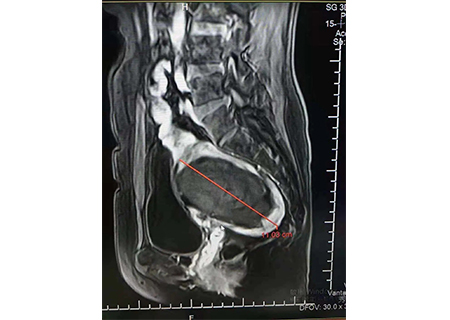

近日,台湾台北秀传医院便有这么一位患者,检查时,发现了14公分的大肌瘤,并且伴有盆腔压迫感,由于该患者不想伤害子宫,所以经过台北秀传医院医师的耐心讲解后,该患者在了解聚焦超声无创治疗的优势后,选择了该技术来消融子宫肌瘤。

14公分相当于一个成年女性的巴掌那么大,对于这么大的肌瘤来说,不仅对医生治疗的要求很高,对设备的要求更加高,精准度、安全性、舒适感等等缺一不可。

消融坏死前14公分

消融坏死后11公分

消融坏死对比图如上↑

治疗后一周追踪,肌瘤已经从14公分降为11公分,患者的盆腔压迫感也减轻很多。